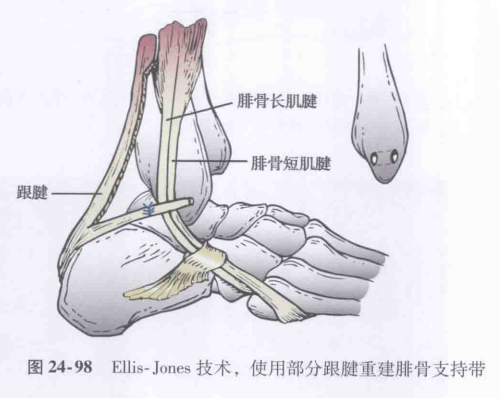

腓骨肌腱脱位的手术类型有:

⑤肌腱重排法。

图源:Coughlin M,Saltzman C,Anderson R,et al. 曼氏足踝外科学 [M]. 第 9 版. 唐康来, 徐林, 译. 北京: 人民卫生出版社,2015:1915.